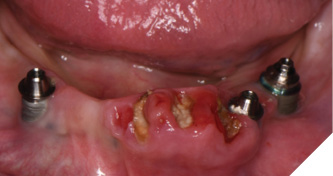

Three weeks later, the patient returned for treatment of the mandible (Figs. 13A, 13B). Teeth 22,23,24 were extracted and implants 19,21 and 27 were removed. A surgical guide with computer guided surgery was used to prepare the osteotomies and place the implants (Figs. 14A, 14B). Implants (Genesis Active – Keystone Dental) were placed in tooth positions 19,20,23,26 and 30. Allograft bone grafts were placed into the extraction sockets and all intraboney defects. Multiunit abutments were inserted on all implants and torqued to 30ncm (Fig. 15). The soft tissues were sutured closed. A rapid denture conversion system was used to efficiently convert a denture into a fixed provisional restoration.20 (EasyPro – Keystone Dental). This denture conversion system maintained the structural integrity of the denture while maintaining an esthetic provisional restoration (Figs. 16A-D).

Fig. 13A

Fig. 13B